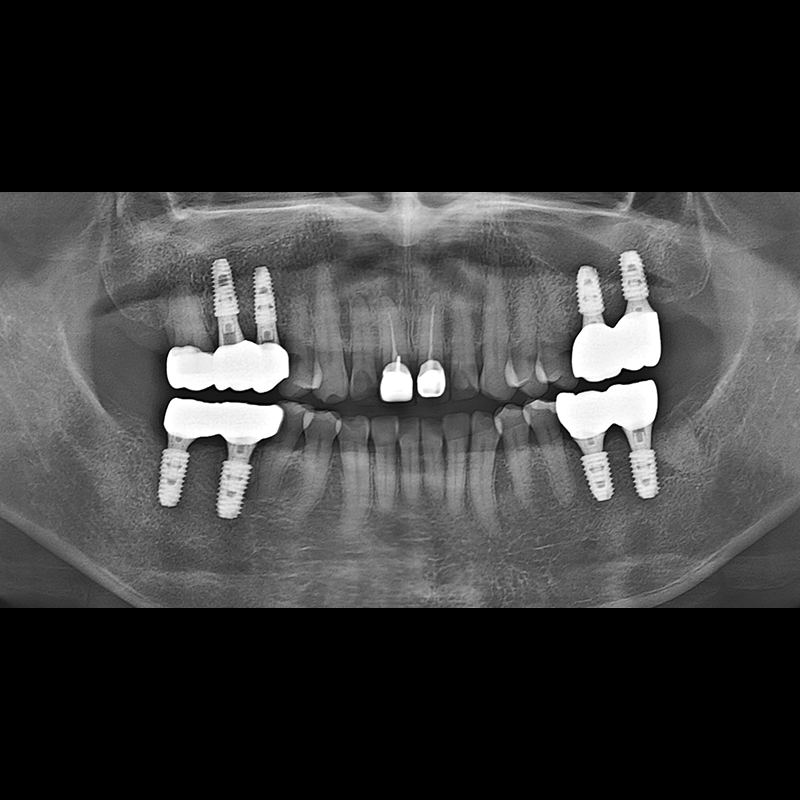

BEFORE AFTER

种植牙前后的照片 2025.05.30

在缺失的牙齿部分和难以挽救的牙齿位置植入了种植牙。